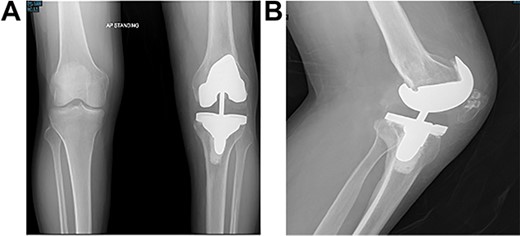

Post-operative plain radiographs from follow-up visits; (A) 3-month post-operative AP radiograph showing implant in place with a lateral gap sized to be 3.2 cm; (B) 3-month post-operative lateral radiograph of the knee showing implant in a satisfactory position.